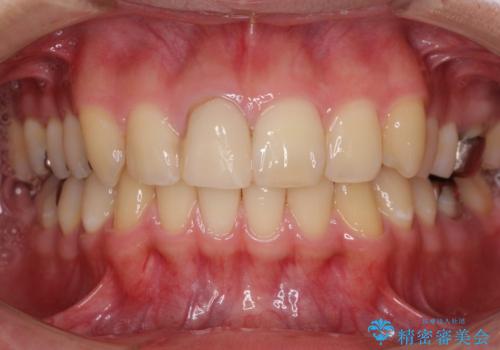

- 治療中の前歯と口腔内にある銀歯が気になるとのことで来院された患者様です。

土台に含まれている金属も含め、口腔内の金属は全て除去し、根管治療が必要な歯は根管治療を行い、オールセラミッククラウンやセラミックインレーにて治療することとしました。

途中来院されない時期があったため、初診から終了まで期間がかかりましたが、根管治療を行った歯の根尖病変はいずれも改善を確認することができました。

口腔内の金属が全てなくなり、患者様には大変満足していただきました。